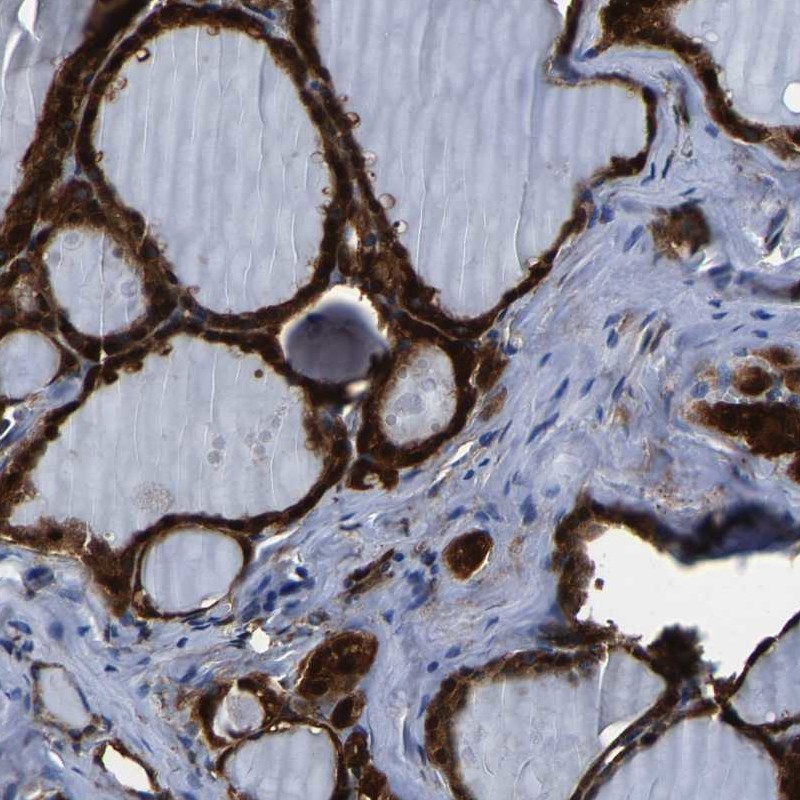

Immunohistochemical staining of human thyroid gland shows strong cytoplasmic and nuclear positivity in glandular cells.